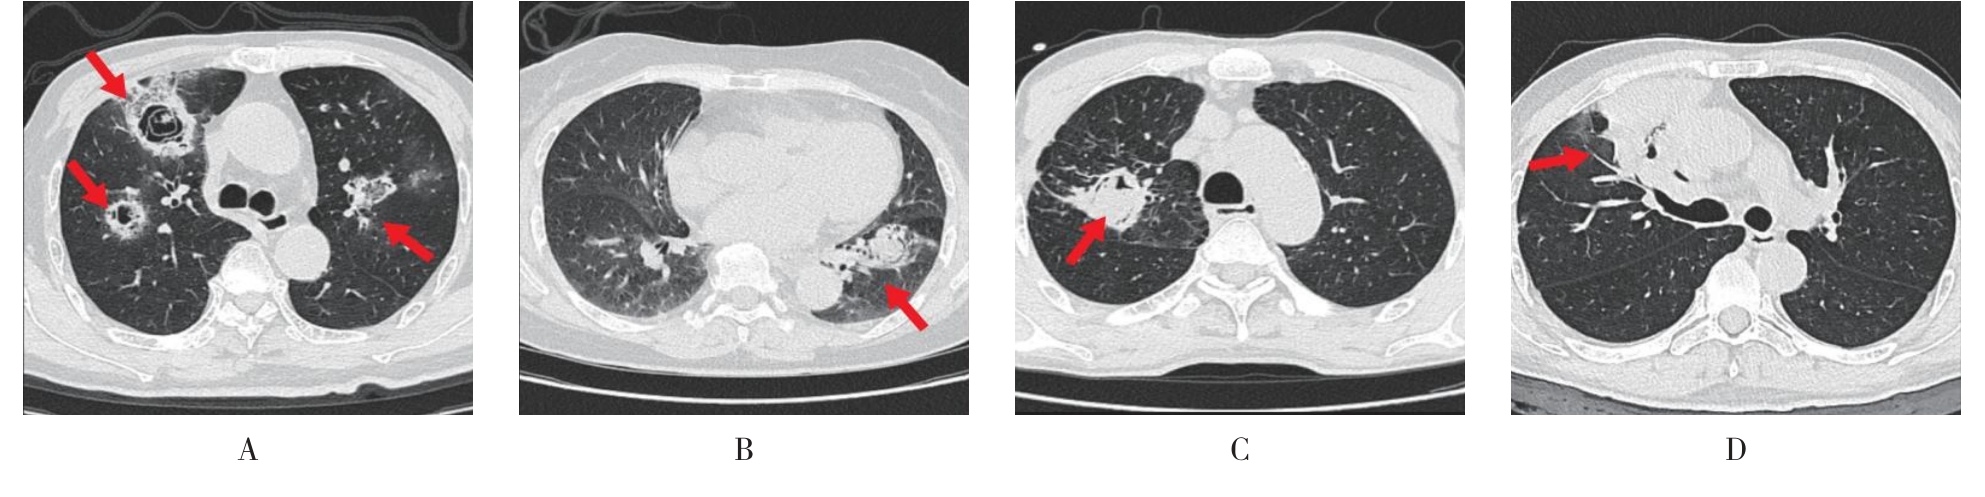

• 侵袭性肺真菌病的支气管镜表现及介入治疗效果

2025, 31(9):81-90. DOI: 10.12235/E20250317

摘要 (112) HTML (56) PDF 6.06 M (77) 评论 (0) 收藏

摘要:目的 探讨侵袭性肺真菌病(IPFD)的支气管镜表现,并评估介入治疗的安全性和疗效。方法 回顾性分析2018年5月12日-2025年5月12日于该院行支气管镜检查的35例IPFD患者的临床资料,观察IPFD的支气管镜表现及介入治疗效果。结果 共收集35例患者临床资料。其中,男22例,女13例,患者年龄(53±14)岁。基础疾病包括:血液系统恶性肿瘤10例,长期应用糖皮质激素者5例,2型糖尿病者4例,肺部恶性肿瘤2例,器官移植1例。胸部CT显示:肺部病变累及单肺叶者19例,累及多肺叶者16例。支气管镜下表现主要为:黏膜充血水肿29例(82.9%)、坏死物堵塞管腔22例(62.9%)、大量黏稠脓性分泌物17例(48.6%)、支气管部分狭窄或闭塞16例(45.7%)、黏膜坏死9例(25.7%)、黏膜出血5例(14.3%)、真菌球3例(8.6%)。其中,32例(91.4%)接受全身性抗真菌治疗,17例(48.6%)接受支气管镜局部两性霉素B灌注治疗,10例(28.6%)采用活检钳钳除病灶,6例(17.1%)采用冷冻探头冻取病灶,4例(11.4%)接受氩气刀治疗。28例(80.0%)临床症状明显改善,肺部影像学病灶缩小或消退;4例(11.4%)病灶稳定;3例(8.6%)未完成治疗。结论 IPFD多见于免疫抑制宿主,支气管镜常表现为:坏死物堵塞管腔、伴脓性分泌物、支气管管腔狭窄和局部黏膜充血水肿或坏死。全身抗真菌药物联合支气管镜下介入治疗,安全性高,且疗效好。